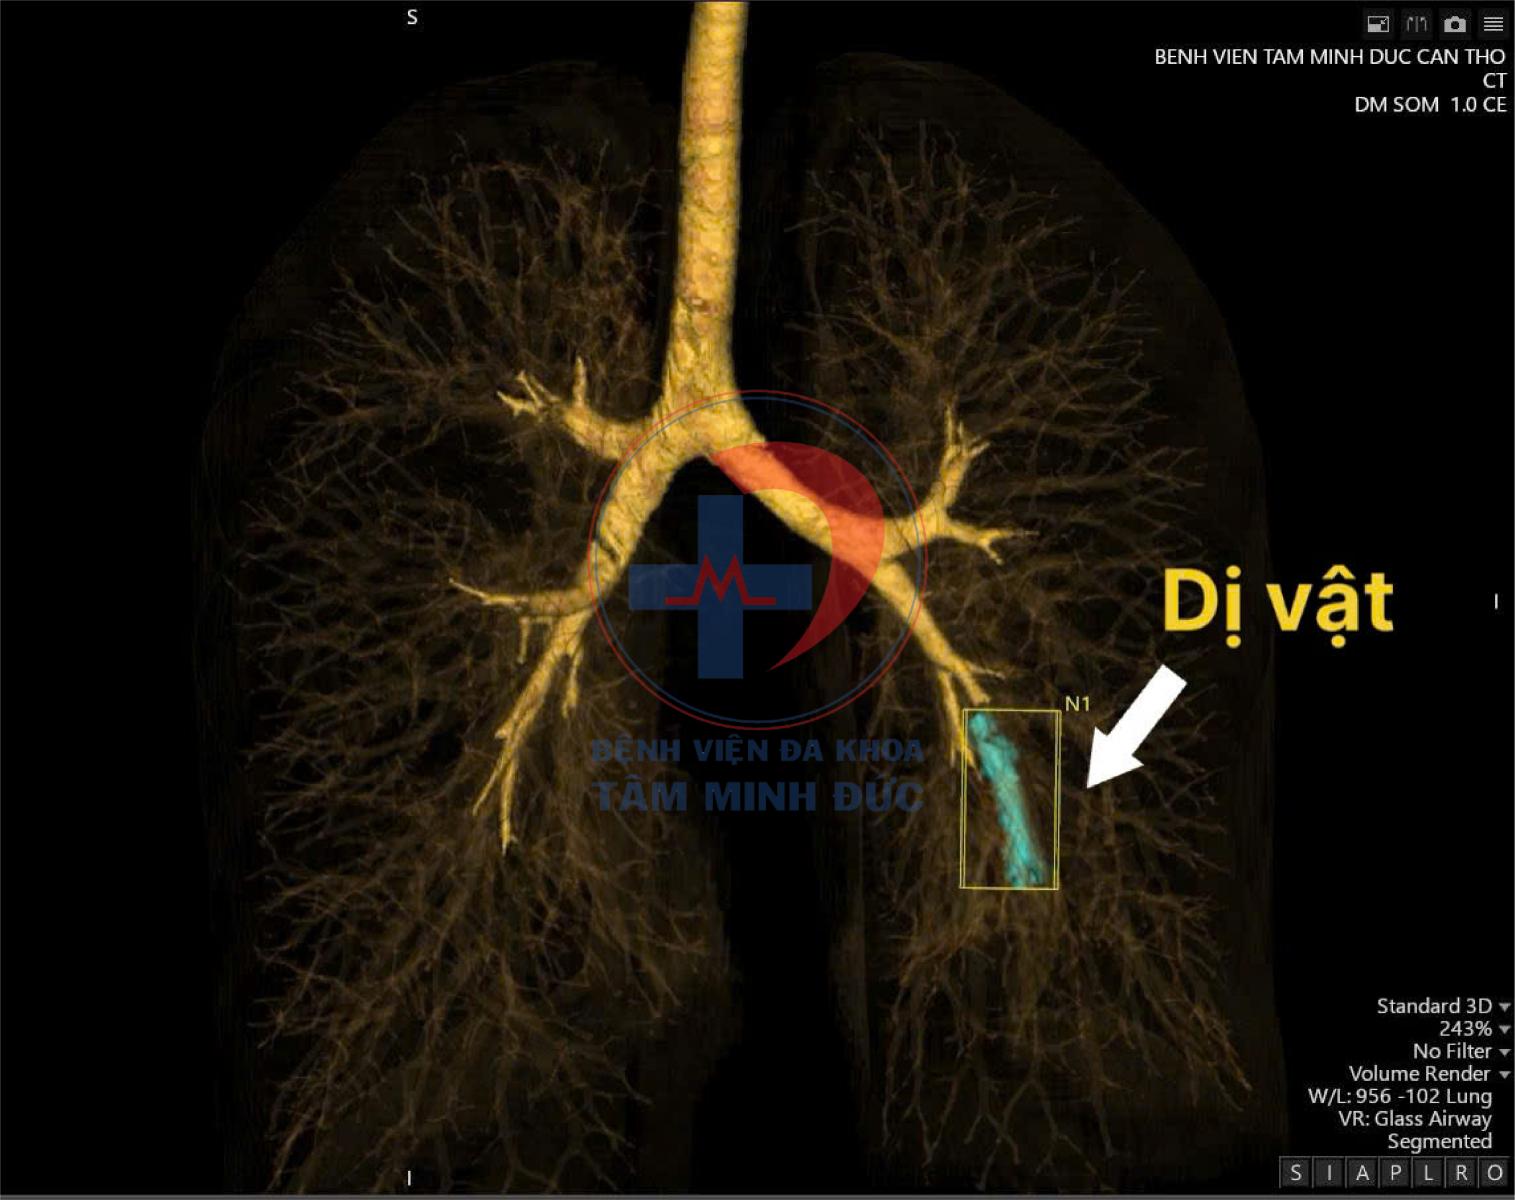

Qua thăm khám và chụp CT ngực có tiêm thuốc cản quang, kết quả cho thấy một dị vật dạng que nằm trong nhánh động mạch nuôi thùy dưới phổi trái. Hình ảnh có mật độ kim khí phù hợp với que tránh thai. Đây là biến chứng lạc chỗ cực kỳ hiếm gặp, nhưng đã từng được ghi nhận ở một số nơi trên thế giới.

Đường kính động mạch phổi lớn hơn kích thước que, máu vẫn lưu thông bình thường nên bệnh nhân có thể không có triệu chứng rõ ràng.

Phát hiện chủ yếu dựa vào chẩn đoán hình ảnh như X-quang, CT-scan.